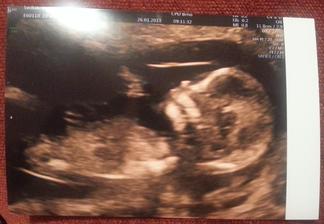

26.1. První screeningové vyšetření: Všechno v naprostém pořádku.

V břiše nam bydlí další princezna ❤ .

Váha stále 66kg žádné přírůstky.